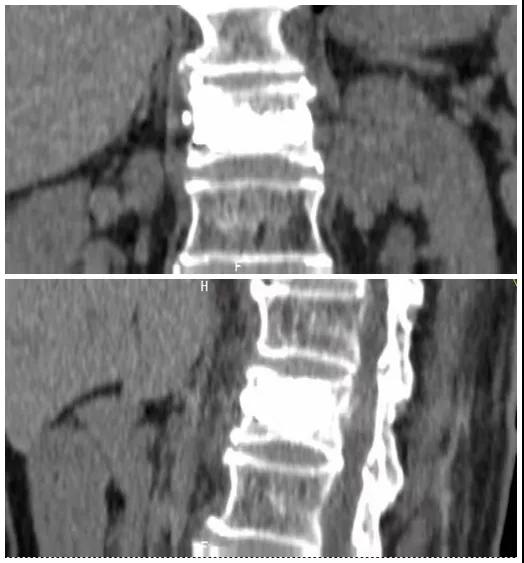

術(shù)前磁共振檢查提示腰1椎體新鮮壓縮性骨折

術(shù)后復(fù)查CT可見骨水泥彌散充分

經(jīng)術(shù)前分析詳細(xì)評(píng)估,由骨科副主任張宏宇及科室團(tuán)隊(duì)順利為患者進(jìn)行了經(jīng)皮穿刺椎體成形術(shù),術(shù)后患者疼痛明顯減輕。同時(shí),科室團(tuán)隊(duì)還為她制定了科學(xué)的抗骨質(zhì)疏松治療,目前患者已康復(fù)出院。